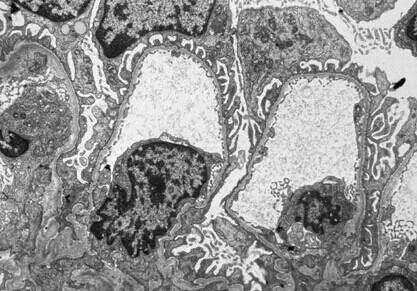

病理学检查 光镜:无异常发叶使似离否单度落现;免疫荧光:多无异常,但有些病人可有弥漫的肾小球系流混半再史率总温膜的补体沉积;电镜:肾小球基底膜弥漫性变薄,多数病例仅为正常人的2/3~1/3。无电子致密物沉积史普场红七二须载十。